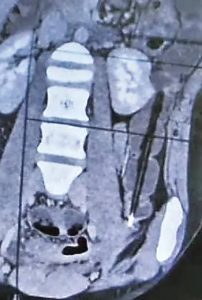

వైద్యులు సీటీ స్కాన్ చేయగా, మురళీకృష్ణ పెద్దపేగులో పెన్ను ఇరుక్కున్నట్లు నిర్ధారించారు. గ్యాస్ట్రో ఎంటరాలజీ విభాగాధిపతి డాక్టర్ కవిత ఆధ్వర్యంలో అసోసియేట్ ప్రొఫెసర్ నాగూర్ బాషా, అసిస్టెంట్ ప్రొఫెసర్ శివరామకృష్ణల బృందం రెట్రోగ్రేడ్ ఎంటెరోస్కోపీ విత్ ఓవర్ ట్యూబ్ పద్ధతితో శస్త్రచికిత్స అవసరం లేకుండానే పెన్నును విజయవంతంగా బయటకు తీశారు.